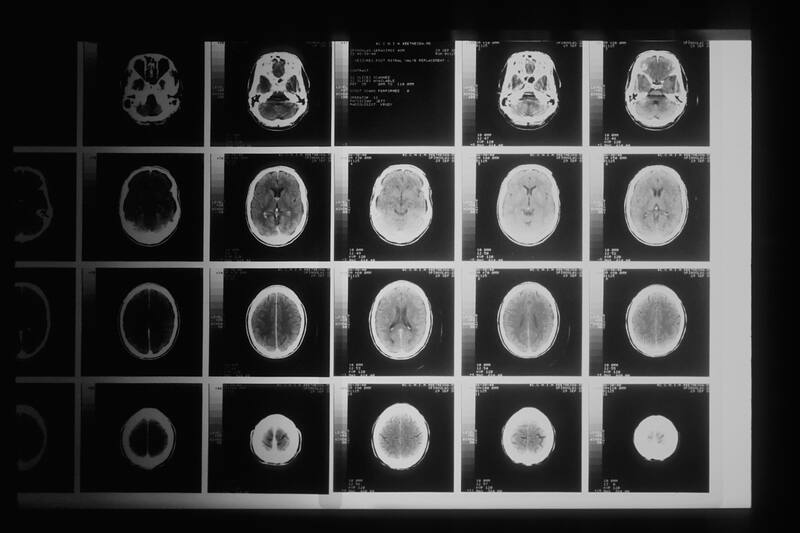

Después de las seis semanas, se le realizó otro escáner cerebral que reveló cambios evidentes en su cerebro, en comparación a la primera imagen que se tomó al empezar el estudio.